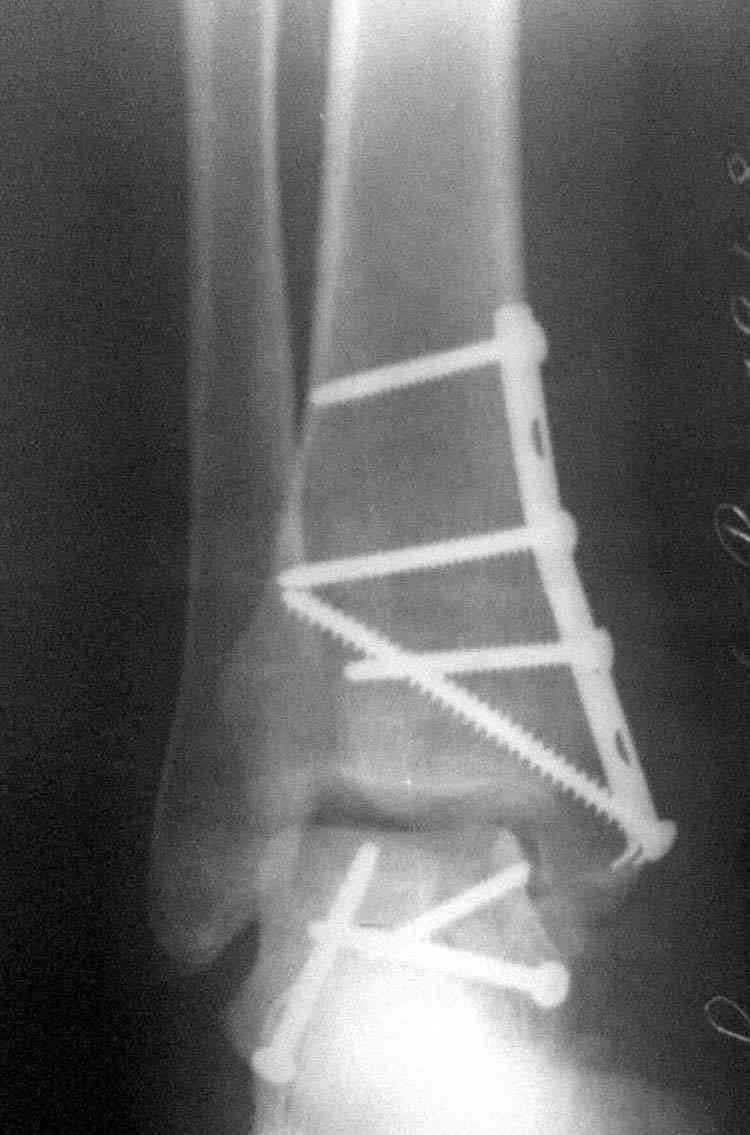

Случай с множественным оскольчатым переломом тарана оперированный из двойного доступа.

Через 2 мес.:

Через 8 мес.:

Через 14 мес.:

Решили не связываться с остеосинтезом, а сделать сразу берцово-пяточный блок. Снимки в приложении.

По завершении удлинения, наверно, заштифтуем.